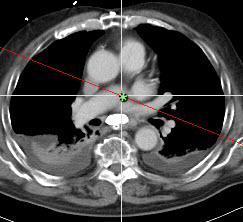

MPR Quadrant view is a Synapse feature that quickly reformats the original image data into orthogonal reconstructions: axial, sagittal, coronal, and oblique planes. Synapse places the reformatted views and original view into a 2x2 tile format in the Viewer as shown in the following examples:

The yellow lines represent the horizontal and vertical axes. The red line displayed on an angle in the reformatted axial is the oblique axis.

As you scroll or move an axis in an image, Synapse automatically synchronizes and scrolls the images in the other views.